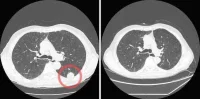

Due to their high degree of accuracy, availability and capability of providing physicians with advanced information, CT scans are commonly conducted in order to diagnose this condition and avoid complications. This imaging means is, however, expensive and exposes patients to ionizing radiation. This could be avoided if there were an alternative.

Comparing paediatric patients aged less than 18 years who had undergone an appendectomy for acute appendicitis pre-algorithm implementation with those post-implementation, researchers evaluated 331 cases over the course of five years. Results showed a decrease of CT use from 39 to 18 percent following the algorithm’s implementation.

Findings also included a 50 percent drop in CT scan use once the algorithm had been implemented. This did not affect the accuracy of diagnosis, offering proof that the reduction of CT use in patient evaluation for appendicitis is indeed a safe and cost-effective step.